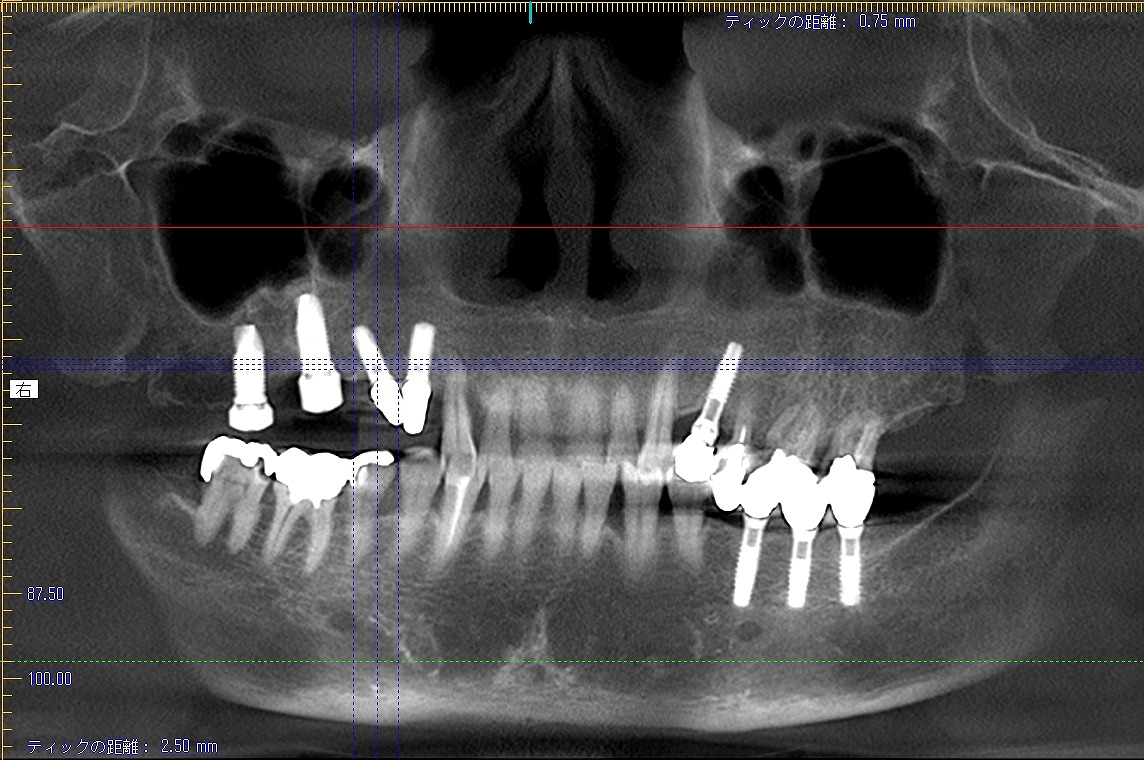

60代女性同じ方の右上6,7番のインプラント埋入について 6番抜歯から数か月おいてインプラントを埋入していきます

60代女性同じ方の右上6,7番のインプラント埋入について 6番抜歯から数か月おいてインプラントを埋入していきます

埋入して2か月後には上部構造を建てていきます

このように綺麗に仕上がりました

4,5番目のインプラントの傾斜がすごいため前述のブログで取り扱ったインプラントになります。

再度補綴が難しかったところになります